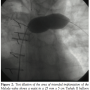

We then proceeded to evaluate the LPA for implantation of the Melody valve (Medtronic). An angiogram in the MPA/proximal LPA region showed occlusion of the proximal RPA and free pulmonary regurgitation with the proximal LPA measuring 18 mm, increasing to 20 mm prior to the origin of the left upper lobe pulmonary artery branch (Figure 1). The distance from the MPA/LPA junction to the origin of the left upper lobe pulmonary artery was confirmed at 26 mm. In order to test the compliance of the lesion and to better assess the size of the narrowest portion of the proximal LPA, a 25 mm x 5 cm Tyshak II balloon (B. Braun) was advanced to the proximal LPA and inflated at low pressure to 2 atm. The waist on the balloon measured 20 mm and the balloon remained in stable position during this inflation (Figure 2). The narrowest portion was at the MPA/proximal LPA, at the previous surgical suture line with the pulmonary artery homograft. We decided to deploy the Melody valve in this area using a 22 mm Ensemble Transcatheter Delivery System (Medtronic). A curved 0.035” Lunderquist Extra Stiff Wire Guide (Cook Medical) was placed in the distal LPA and the system was advanced with relative ease to the LPA where it was positioned. Multiple angiograms through the side port were performed to accurately position the valve and place it proximal to the origin of the left upper lobe pulmonary artery. The inner and outer balloons were inflated sequentially and then deflated. The outer balloon was then inflated to slightly higher pressure. There was a residual waist seen in the mid portion of the stent measuring about 20 mm at the origin of the LPA from the MPA. Pullback pressures demonstrated a 4 mm Hg systolic gradient from the distal LPA to the MPA across the valve. Repeat angiography showed excellent valve function with no compromise in flow to the left upper lobe branch pulmonary artery and no regurgitation (Figure 3). A transthoracic echocardiogram the next day confirmed excellent valve function with trivial regurgitation through the valved stent.

Pre-catheterization assessment by MRI (or CT when applicable) prior to percutaneous implantation of pulmonary valves is helpful for pre-procedure planning. The predicted length from the MPA to the left upper lobe origin was deemed adequate by MRI and reconfirmed by angiography. This is an important consideration, as the Melody valve is a covered stent, and we did not want to cover any of the left pulmonary artery branches. We deliberately deployed the very proximal portion of the Melody valve in the MPA, not only to center the stent, but also to avoid covering the origin of the left upper lobe pulmonary artery. Another important consideration is the use of pre-dilation. Pre-dilation not only allowed us to evaluate the compliance of the vessel at the implantation site, but also allowed us to assess stability of the balloon, and thus gauge stability of the Melody valve during deployment. Stability of any stent may be an issue in the absence of sufficient stenosis in the face of regurgitation. In our case, the fact that there was a mild narrowing at the MPA/LPA junction from previous surgery was advantageous, as it allowed for an “anchoring zone” for our stent. Since there was adequate stability during this maneuver, we did not feel the need to rapidly pace the RV for stability of the valve. However, this should be considered in circumstances like ours12 if there is any concern for excessive movement during test dilation or if a focal narrowing is not present.